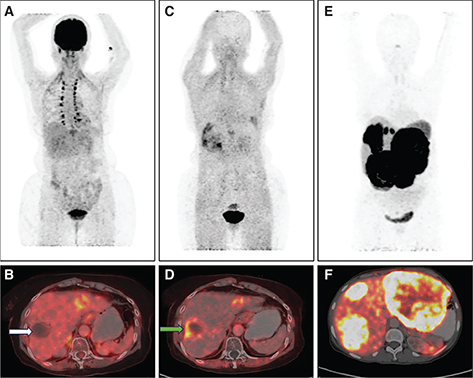

Fibroblasts associated with malignancy are known to be involved in tumor growth, migration, and progression. Fibroblast activation protein (FAP) is a serine protease highly expressed in cancer associated fibroblasts (CAF). As CAFs make about 90% of the gross tumor mass, targeting FAP inhibitor (FAPI) for imaging can aid in the visualisation of the tumor stroma. Guo et al. compared CECT, liver MRI, 68Ga-FAPI and 18F-FDG PET/CT in diagnosing primary and metastatic lesions in patients with HCC. Thirty-four individuals with hepatic lesions were included in the study and underwent concomitant 68Ga-FAPI-04, 18F-FDG PET, and CT scans. In the detection of primary liver tumors, the sensitivities of CECT, MRI, 68Ga-FAPI-04, and 18F-FDG PET/CT were found to be 96%, 100%, 96%, and 65%, respectively (19). 68Ga-FAPI PET/CT also has the potential to open the door for theranostic treatment option with therapeutic radionuclides in select patients showing 68Ga-FAPI uptake. Figure 2 (A-D) shows comparison of 18F-FDG and 68Ga-FAPI PET in a case of HCC.

Fig 1

Figure 2. 18F-FDG, 68Ga-FAPI PET/CT in HCC and 68Ga-DOTANOC PET/CT in NET. A. Maximum Intensity Projection (MIP) image of 18F-FDG PET/CT showing increased tracer uptake in the left lobe of liver in a case of HCC. Corresponding fused 18F-FDG PET/CT (B) image shows a non-FDG avid lesion in segment VII of liver (white arrow) and FDG avid lesion in left lobe. C. MIP image of 68Ga-FAPI PET/CT in the same patient showing areas of increased FAPI uptake in both lobes of the liver with corresponding fused transaxial 68Ga-FAPI PET/CT (D) image showing FAPI avidity (SUVmax 9.8) in the same segment VII and left lobe liver lesions (green arrow). 68Ga-FAPI PET can detect more lesions with higher tracer uptake compared to 18F-FDG PET-CT in HCC. E. MIP image of 68Ga-DOTANOC PET/CT in another patient with neuroendocrine tumor showing intense tracer uptake in the liver in multiple areas. Corresponding fused axial PET/CT image (F) shows intensely somatostatin receptor expressing lesions in both lobes of the liver, consistent with metastatic NET. 68Ga- DOTANOC PET/CT is highly specific for neural crest origin tumors.

Molecular imaging methods useful in diagnosis, staging and metastasis evaluation of NETs include 111In-pentetreotide somatostatin receptor scintigraphy (111In-SRS), 68Ga-DOTATATE, 68Ga-DOTANOC, and 18F-DOPA PET/CT for well-differentiated tumors and 18F-FDG PET/CT for high grade tumors. Somatostatin receptor (SSTR) overexpression is present in 60–90% of these tumors and is an essential mechanism for SRS. Of these, somatostatin receptor subtype 2 is expressed by 85% of NETs. Recent experience with 68Ga-labeled somatostatin analogue PET imaging shows higher sensitivity as compared to 111In-SRS and 99mTc-SRS. 111In-SRS and 99mTc-SRS are used less due to lower sensitivity and resolution compared to 68Ga-DOTA-NOC/TATE PET/CT. The diagnostic efficacy of 68Ga-DOTATATE PET/CT was compared to that of 99mTc-octreotide SPECT/CT and CT/MRI by Fallahi et al. In this prospective study, 25 NET patients who had been referred for an octreotide scan for suspected or proven NET were included. On a patient-based analysis, the sensitivity for CT/MRI, 68Ga-DOTATATE PET/CT, and 99mTc-octreotide SPECT/CT, respectively, was 71%, 90%, and 65%. The specificity of 99mTc-octreotide SPECT/CT, 68Ga-DOTATATE PET/CT, and CT/MRI was 80%, 80%, and 75%, respectively (21). Figure 2 (E-F) shows 68Ga-DOTANOC PET/CT images in a case of metastatic well-differentiated NET.